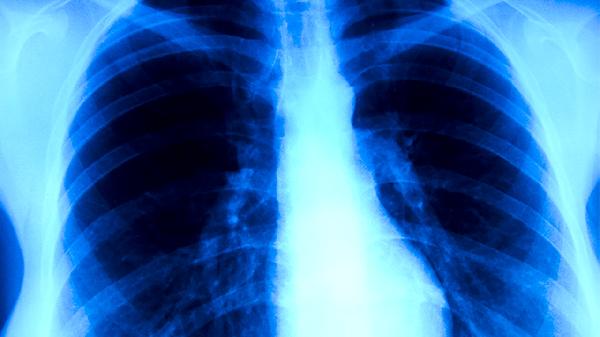

肺結(jié)核發(fā)病的癥狀和體征主要有咳嗽、咳痰、咯血、胸痛、發(fā)熱等。肺結(jié)核是由結(jié)核分枝桿菌感染引起的慢性傳染病,主要通過(guò)呼吸道傳播,患者需及時(shí)就醫(yī)進(jìn)行規(guī)范治療。

肺結(jié)核患者咳痰多為白色黏液痰,合并細(xì)菌感染時(shí)可變?yōu)辄S色膿性痰。部分患者痰中帶血絲或出現(xiàn)大量咯血??忍蹬c肺部炎癥反應(yīng)導(dǎo)致分泌物增多有關(guān),嚴(yán)重時(shí)可能提示存在空洞型肺結(jié)核?;颊咝柽M(jìn)行痰涂片檢查以明確診斷,并遵醫(yī)囑使用乙胺丁醇片、鏈霉素注射液等藥物。

肺結(jié)核患者出現(xiàn)咯血多因病灶侵蝕血管所致,可表現(xiàn)為痰中帶血或大量咯血??┭繌纳倭垦z到數(shù)百毫升不等,嚴(yán)重時(shí)可導(dǎo)致窒息??┭R?jiàn)于空洞型肺結(jié)核或支氣管內(nèi)膜結(jié)核,患者需立即就醫(yī),醫(yī)生可能建議使用止血藥物如氨甲環(huán)酸注射液,必要時(shí)需進(jìn)行支氣管動(dòng)脈栓塞術(shù)。